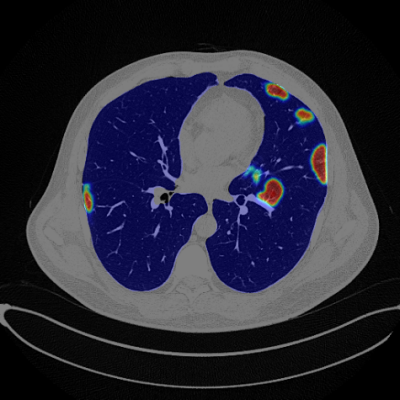

A COVID-19 chest CT heat map from RADlogics

“There is significant potential clinical impact in the application of AI to medical images to follow and predict trajectory of disease,” said Eliot Siegel, M.D., Professor and Vice Chair at the University of Maryland School of Medicine, Department of Diagnostic Radiology and Chief of Radiology and Nuclear Medicine for the Veterans Affairs Maryland Healthcare System. “Some of the early research that I did in collaboration with RADLogics was in the rapid utilization of machine learning to find and quantify disease in thoracic CT scans of patients with COVID-19. In order to streamline a process that normally might take years to just a few weeks, it was critical to apply transfer learning to existing tools and software to rapidly develop these algorithms.”

“The ability of medical imaging – in combination with AI – to discover and quantify the burden of COVID-19 has been well documented. There would be tremendous clinical value in an AI algorithm that could establish and utilize a trajectory of change to predict which subset of patients might need more intense therapy such as mechanical ventilation, which subset of patients could be more confidently discharged, and predict subsequent clinical course,” added Siegel. “Today, there are many promising AI applications that have emerged that could allow us to address the major challenges that have hit the healthcare sector during the pandemic, and beyond as we plan to treat patients with COVID-related complications and as we provide diagnostic and therapeutic procedures that were delayed during the surge.”